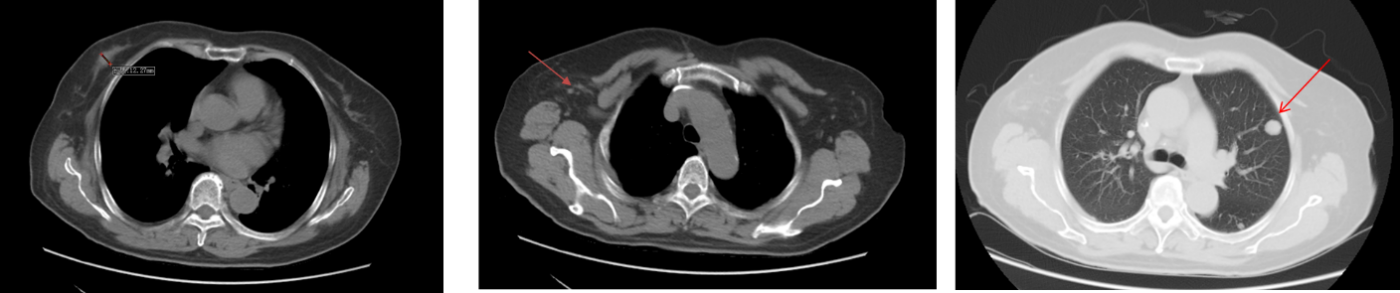

2019 年 10 月胸部 CT :两肺多发转移,排除颅内及骨转移。

图2 CT影像

2020 年 11 月复查胸腹盆 CT 提示右乳软组织影增大、肺结节数目增多且体积增大,评估疾病进展(PD)。

影像学结果(右乳软组织+肺结节)如下图所示:

图3 影像学变化(1)

图4 影像学变化(2)